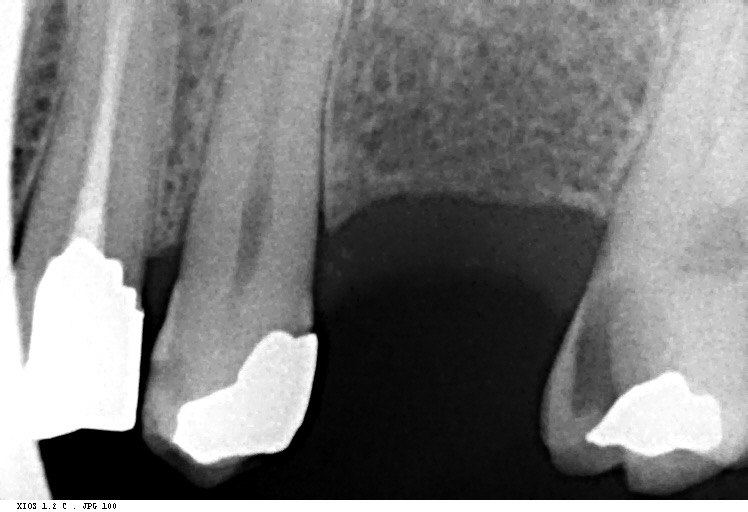

36. What options cannot be selected for the tooth # 3.7?

37. What options can be selected for tooth # 1.2?

38. What option can be seen in the print of this X ray?

39. What options can be selected for the print of this X ray?

40. What cannot be seen in the print of this X ray?

41. What options cannot be selected for the print of this X ray?

42. What options can be detected for this X ray?

43. What can be selected for the print of the X ray?

44. What option cannot be seen in this X ray?

45. What options are incorrect regarding this X ray?

46. What options cannot be seen in the print of this X ray?

47. What option can be selected for the following X ray?

48. What options cannot be seen in the print of the X ray?

49. What option cannot be selected for the print of this X ray?

50. What option can be selected for this X ray?